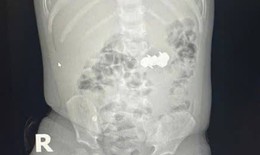

Việt kiều Mỹ 73 tuổi lựa chọn về Việt Nam phẫu thuật khối u đại tràng ác tính

Camera bệnh viện - 10/10/2025 14:55SKĐS - Việt kiều Mỹ 73 tuổi quyết định đến Bệnh viện Đa khoa Thủ Đức để thăm khám sau khi xuất hiện các dấu hiệu bất thường về đường tiêu hóa. Kết quả phát hiện khối u đại tràng ác nên nhanh chóng được phẫu thuật cắt bỏ.